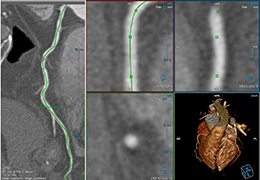

View X-Ray CT & MRI Scans Fast and Easily

Designed for surgeons, Pro Surgical 3D makes it easy to view patient scans quickly. Pro Surgical 3D facilitates the optimal 3D treatment and assessment workflows based on X-ray CT and MRI scans – and best of all, it’s FREE!

High-quality and fast 3D reconstruction and 3D rendering

Performs 3D reconstruction and volume rendering.

Multi-planar slicing.

Oblique slicing.

Instant and interactive surface extraction and export to STL and PLY formats.